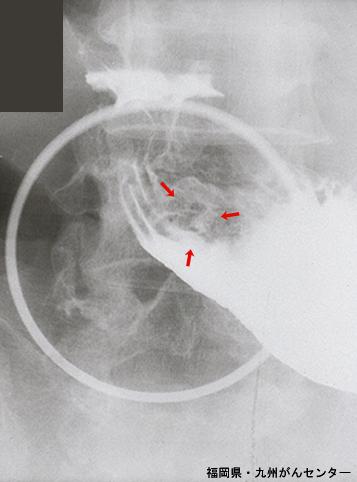

症例提示(所在地,施設名等): 福岡県・ 九州がんセンター

疾患(病理主体)の分類良性上皮性腫瘍/腺腫

部位(臓器別)胃(部位)/前庭

検査方法X-P

腫瘍の肉眼分類0型(表在型)/IIc型(IIc)

病変の最大径(ミリ)10〜14